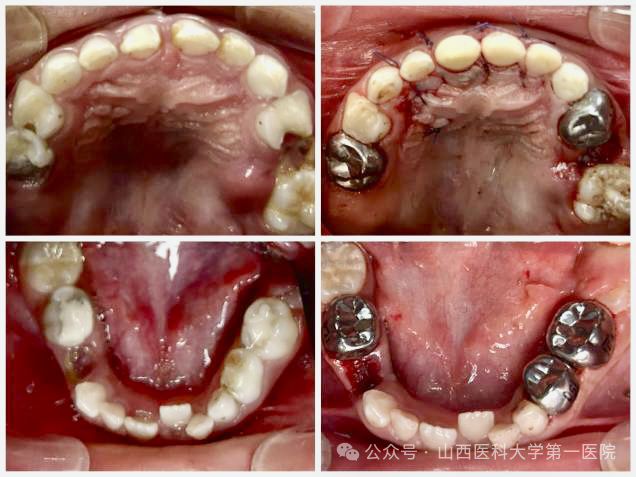

口腔内科儿童口腔团队在日间手术中心为一名6岁患儿在全麻下完成17颗牙齿的治疗,通过一站式精准干预解决了患儿复杂口腔问题,避免了多次治疗对患儿心理健康带来的不利影响。

手术当天在麻醉科经鼻插管全气道管理全身麻醉下,口腔内科采用微创去腐复合树脂美学修复、牙髓根管治疗、牙髓切断术以及预成冠技术恢复患牙的形态及功能;口腔颌面外科团队微创拔除2颗埋伏牙多生牙,患儿术后2小时完全苏醒,经观察无任何不适于第二日上午离院。